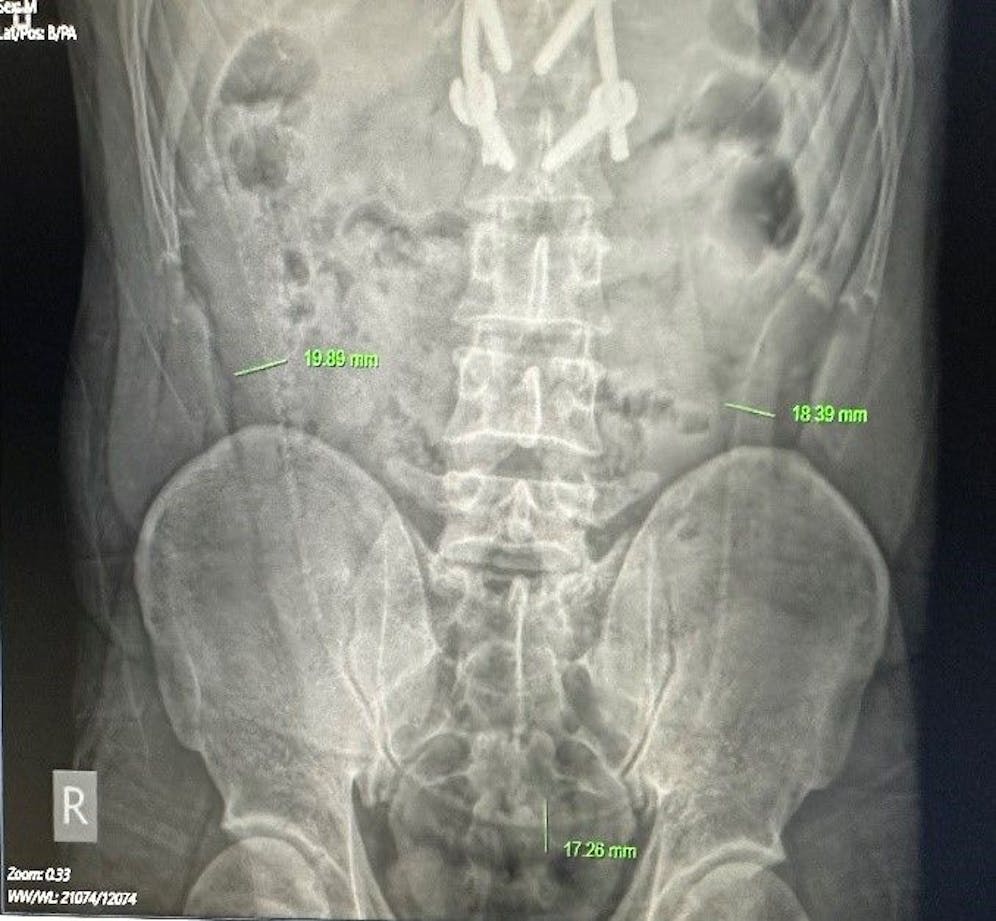

Ein 31-jähriger Inder ist Ende Juli in einer äußerst prekären Lage in das Vietduc-Uniklinikum in Hanoi, Vietnam, auf dem OP-Tisch gelandet. Der Mann war mit extremen Bauchschmerzen aufgenommen worden, doch bei ihrer Untersuchung machten die Ärzte einen schockierenden Fund. Wie die "Times of India" berichtet, leuchtete auf dem Röntgenbild ein komplettes Tier-Skelett im Bauchraum des Mannes auf!

Der 31-Jährige hatte sich offenbar einen lebenden Aal anal eingeführt. Der Fisch hatte in Panik die Flucht durch das Rektum nach vorne angetreten und sich dann mit seinen scharfen Zähnen durch die Darmwände gebissen, lag nun mitten in der Bauchhöhle.

Dabei konnten sowohl der rund 63 Zentimeter lange Anal-Aal sowie die Zitrusfrucht erfolgreich entfernt werden. Zur Sicherheit wurde noch nach weiteren Fremdkörpern gesucht. Dazu wurde ein künstlicher Darmausgang gelegt, damit es nicht zu einer weiteren Infektion der Bisswunde und dem dahinterliegenden Bauchraum kommt.